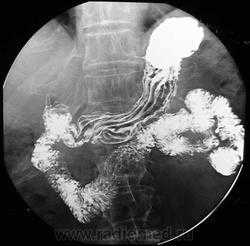

Рельеф слизистой желудка. Для желудка характерны: а) продольные складки, располагающиеся параллельно малой кривизне; б) ячеисто-трабекулярные складки – короткие, извилистые, косо и далее поперечно направленного вида с множеством анастомозов. В области тела желудка идут 5-8 продольных складок шириной 0,3-0,5 см.

Двойное контрастирование. Сущность заключается во введении в полость исследуемого органа небольшого количества (чтобы обмазать стенки органа) бариевой взвеси, после чего через зонд вводят определенное количество воздуха. При исследовании желудка используют также «метод шипучки», т. е. прием слабого раствора лимонной, винно-каменной или уксусной кислоты, и вслед за ней — небольшого количества растворенной двууглекислой соды. В результате в желудке выделяется некоторое количество углекислого газа. Использование двойного контрастирования позволяет отчетливо выявить детали рельефа внутренней поверхности исследуемого органа на фоне газовой среды — воздуха, кислорода или углекислого газа.

При диагностике гастритов данные рентгенографии неспецифичны и лишь в случае гипертрофического или склерозирующего (ригидного) гастрита можно увидеть грубые изменения рисунка слизистой (гипертрофия или сглаживание, ригидность стенок).

Классическим показанием к рентгенологическому исследованию желудка является диагностика язв желудка и 12-перстной кишки. Язвы желудка чаще всего локализуются на малой кривизне, а 12-перстной кишки - в области ее луковицы. Однако возможна любая локализация язв. Наиболее надежными рентгенологическими симптомами язв являются симптомы «ниши» и «кратера», локальные изменения рисунка слизистой, отек и ригидность стенки в месте локализации язвы